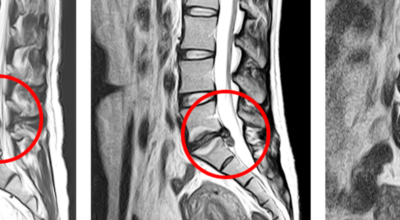

경추 사이의 추간판(디스크)이 탈출 또는 파열되어 경추신경이 자극이나 압박을 받아 통증이 생기는 증상을 말해요. 경추는 운동성이 큰 부위로 추간판이 압력을 받으면 튀어나와 척수나 신경을 압박하게 되는데요 목디스크는 퇴행성 변화 이후에 발생되기 때문에 많은 환자들이 만성적인 통증을 지니고 있는 경우가 많아요. 급성으로 생기는 경우는 교통사고, 추락, 스포츠 활동에 의한 목 부상으로 나타나기도 해요. 20대부터 가벼운 초기 증상으로 시작하여 옳지 않은 습관으로 악화되거나 호전되기를 반복해요. 나이가 들면 퇴행성 변화로 40~50대에 가장 많은 환자 수를 보인다고 합니다

옳지 않은 자세만으로 목디스크증상이 생기는 것은 아니에요. 나이가 들어 노화 현상으로 인하여 퇴행하기 시작하면서 변화가 일어나는 경우도 있습니다. 스마트폰과 태블릿이 보급되기 전에는 이 현상이 주원인이 되어 높은 노년층에서 많이 나오는 질환이었으나 요즘엔 전자기기가 발달하고 들어오면서 젊은 층에서도 발병을 하고 있어 이제는 어느 한 세대에 특화된 병변이 아닌 모든 세대에서 발생할 수 있는 흔한 일입니다. 그리고 외상으로 인한 쇼크으로 디스크가 생기게 될 수 있는데, 이 경우, 후에 나타나는 후유증도 함께 따라올 수 있어 평소 관리가 중요해요.